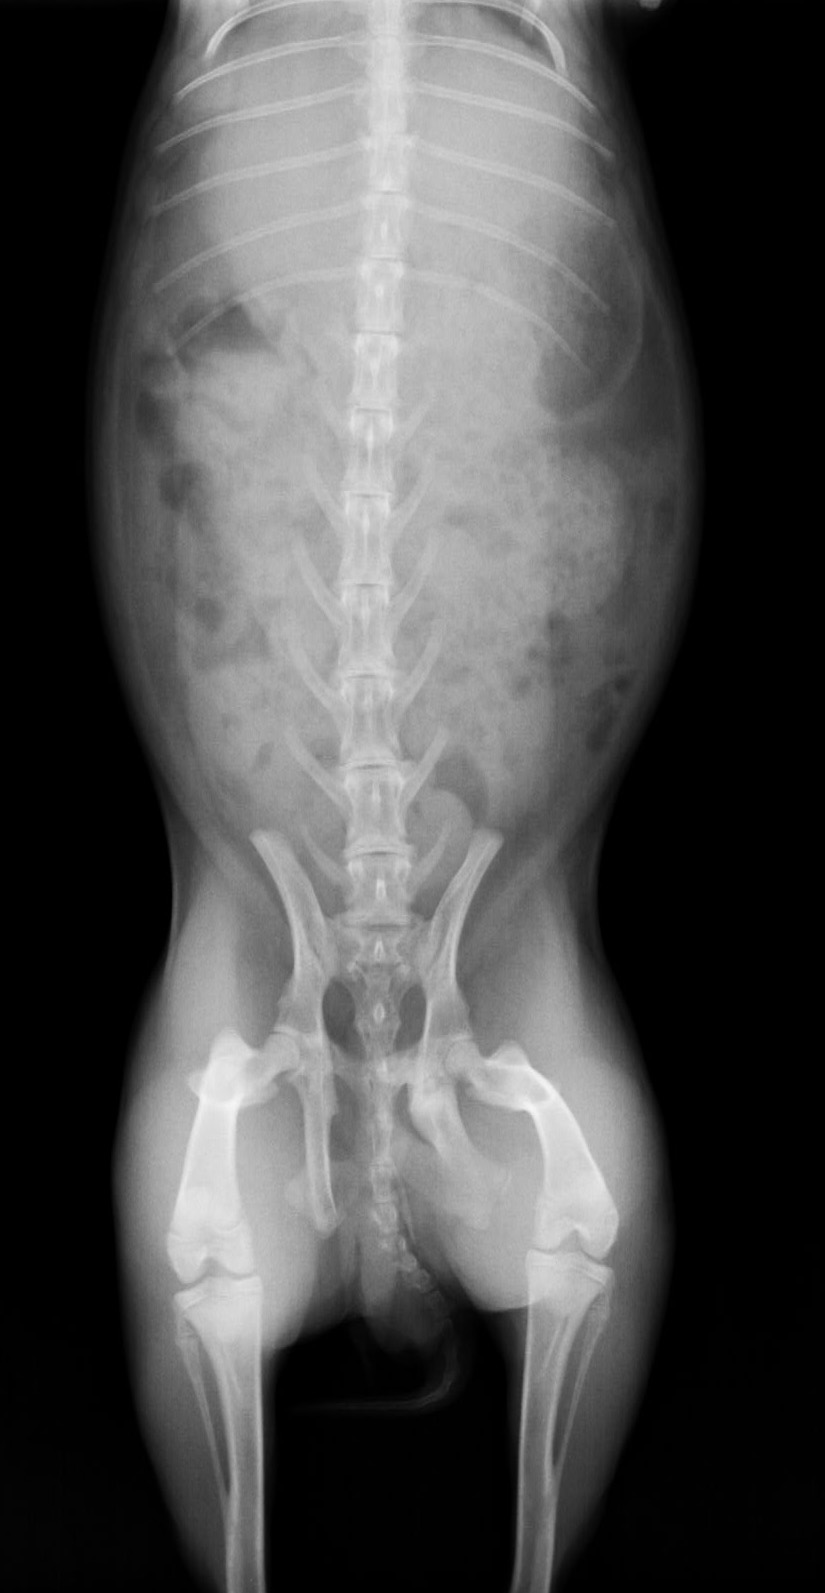

ウサギの骨盤骨折

この症例は骨盤を骨折しており、左骨盤腸骨の股関節の下が骨折しています。また恥骨結合側も骨折してる。

骨端線がはっきりしているので成長期のウサギということがわかります。

比較的変異が少ない場合手術固定するよりもそのまま安静にする方が結果としてよい場合があります。

他の合併症(出血や内臓の障害)に注意します。

骨折の場所が内側に入り込んでいるので完治するまでにもう少し内側に入りこむと思われます。

その場合便秘、排尿障害、雌の場合は出産困難などが考えられます。